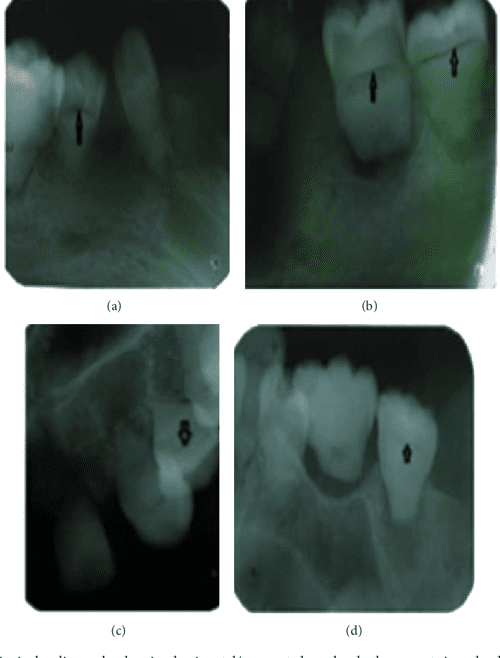

Radiographic findings of dental changes. A) Microdontia in the upper Dental Radiographic Findings The american dental association’s (ada) council on scientific affairs, in collaboration with the u.s. Familiarity with the imaging appearance of common dental conditions, such as hyperdontia and hypodontia, tooth trauma, periodontal disease, caries, periapical disease,. Radiographic imaging is an integral part of the diagnostic process in clinical dentistry. A systematic and repeated approach to examining panoramic radiographs, which is recommended. Dental Radiographic Findings.